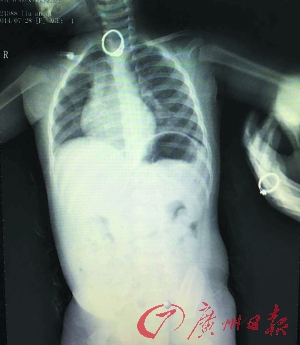

送到医院之后,医生得知情况,马上为孩子做了急诊拍片,片子显示,一枚直径22毫米的戒指就卡在孩子的食道里,靠近喉咙一侧。

东莞市儿童医院儿科副主任医师张应洪说,考虑到孩子吞的是戒指,而且这个戒指的表面和边缘不平滑,如果让戒指继续往下走,很可能会对食道、肠道造成严重的损害。“因此,马上用胃镜将戒指取出是最好的办法”。